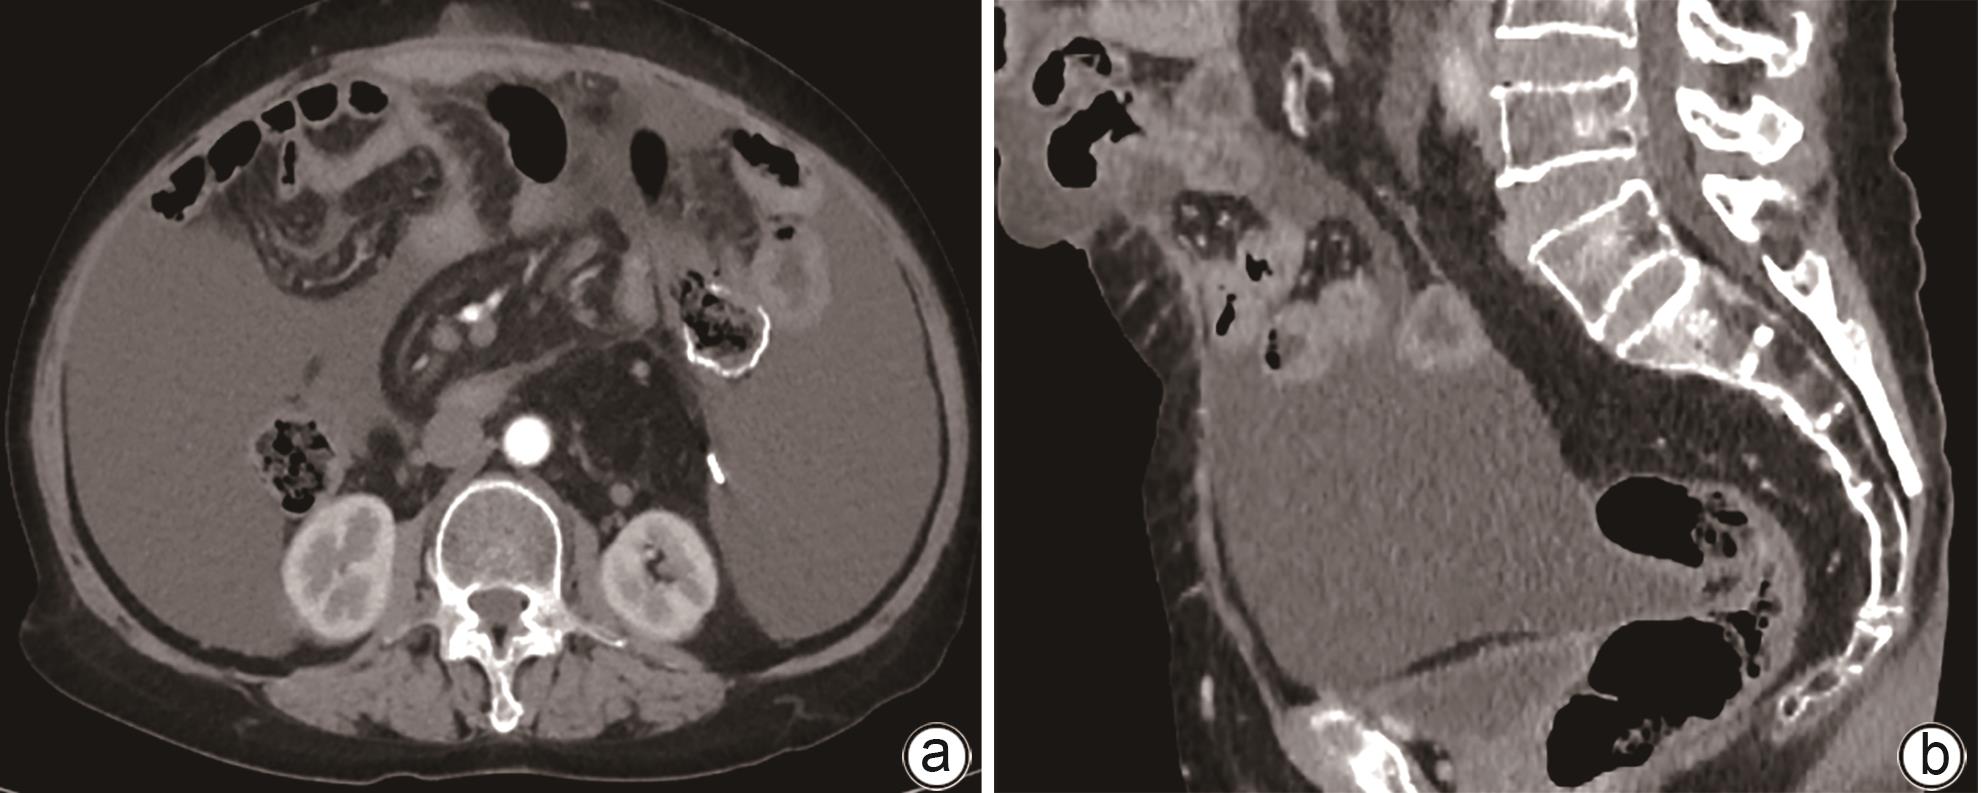

病例报告

失代偿期肝硬化合并多原发癌1例报告

晁文婷, 黄睿

2024, 40(9): 1868-1872. DOI: 10.12449/JCH240923

摘要(912) HTML (383) PDF (1776KB)(105)

摘要:

多原发癌是指在同一个体中存在一种以上的具有不同组织学和部位的癌症,临床较为罕见。本文报告1例肝硬化失代偿期合并多原发癌的病例,主要讨论了肝硬化失代偿期患者合并多原发癌的诊治经过及临床启示。